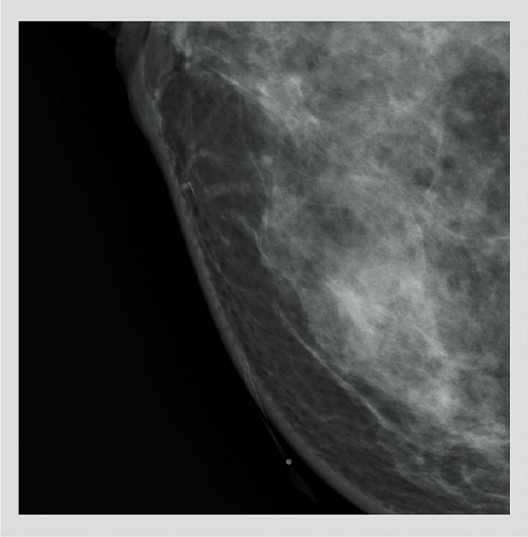

29kV 44mAs 0.83mGy

33mm 102N

34mm 62.8N